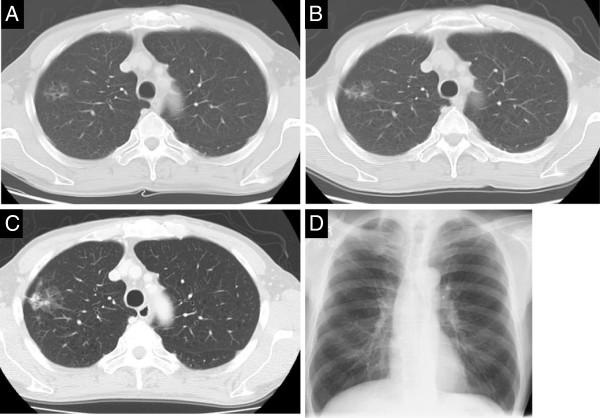

A 67-year-old man underwent abdominoperineal resection for rectal carcinoma in June 2008. A ground glass opacity had been identified in the upper lobe of the right lung and was gradually enlarging. In March 2012, bronchoscopic cytology for investigation of the mass revealed non-small cell lung cancer, suggesting primary lung non-small cell carcinoma (T1bN0M0, Stage IA). When he was referred to our hospital for surgery, his complete blood count showed a red blood cell level of 6.50×106/μL, hemoglobin of 21.0 g/dL, and hematocrit of 60.1%. The hematologists' diagnosis was secondary polycythemia due to heavy smoking (smokers' polycythemia) because the white blood cell and platelet counts were within normal limits and the erythropoietin was not increased. We calculated the appropriate phlebotomy and infusion volumes based on a formula that we modified. After 550 g of blood was phlebotomized to reduce the hematocrit to approximately 55%, video-assisted right lung upper lobectomy with lymph node dissection was performed in April 2012. The hematocrit was maintained at <50% postoperatively, and the patient was uneventfully discharged on postoperative day 7. The predictive hematocrit and measured hematocrit were very closely approximated in this case.

一名67岁男性于2008年6月接受了腹会阴联合直肠癌切除术。右肺上叶发现磨玻璃影且逐渐增大。2012年3月,对该肿物进行支气管镜细胞学检查显示为非小细胞肺癌,提示原发性肺非小细胞癌(T1bN0M0,ⅠA期)。当他因手术转诊至我院时,其全血细胞计数显示红细胞水平为6.50×10⁶/μL,血红蛋白为21.0 g/dL,血细胞比容为60.1%。血液科医生诊断为重度吸烟所致继发性红细胞增多症(吸烟者红细胞增多症),因为白细胞和血小板计数在正常范围内且促红细胞生成素未升高。我们根据改良公式计算了合适的放血量和输液量。放血550 g以使血细胞比容降至约55%后,于2012年4月进行了电视辅助右肺上叶切除术及淋巴结清扫术。术后血细胞比容维持在<50%,患者于术后第7天顺利出院。在该病例中,预测的血细胞比容与实测的血细胞比容非常接近。